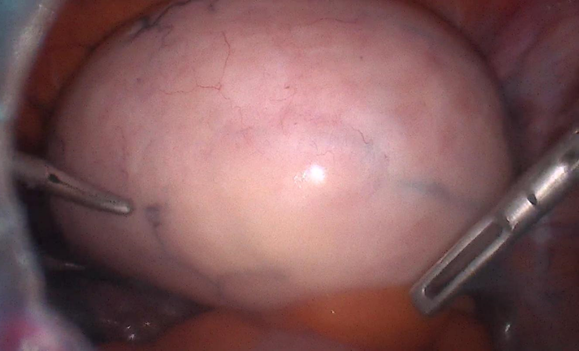

Intraoperative images

1. Intraoperative image visualized as right ovarian fibroma.

1. Right ovarian fibrothecoma, with dilated and elongated infundibulopelvic ligament.

1. Normal uterus and left adnexa. Right fibrothecoma with evidence of extreme fimbria.

1. Surgical piece: ovary and right tube.